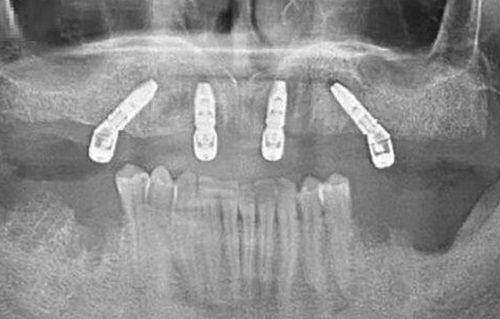

微创种植:相较于传统种植牙项目,微创种植会在手术前结合优质的医疗技术设备以及口腔扫描仪等获取口腔更详细的信息,评估顾客种植牙的路线方向与深度,并在可预估的条件下按路线进行控制操作。这样获得的种植结果更稳定,对牙齿内部神经血管的伤害也更小。

无锡北极星口腔门诊部开设了丰富的诊疗项目,包括ALL - ON - 4技术、即刻种植技术、隐适美隐形矫正(美进口)、传统正畸技术、美国Beyond蓝光美白、不磨牙瓷贴面技术、仿生美牙冠技术、美国3M纳米树脂补牙技术、龋齿祛腐新技术、牙周病分型治疗技术等。

由无锡北极星口腔门诊部发起的“无锡数字化口腔种植联盟”,汇聚五大口腔供应商,达成强强联手的协定,帮助更多需要口腔服务的群体。每一颗牙都拥有专属的身份证(产品ID),顾客可通过相关通道索引获取产品相关信息,该机构也为每一颗牙提供品质售后。门诊部引进了大批医疗设备,如德国卡瓦3D exam全视野口腔锥形束CT、德国KaVoKey laser3水激光、德国卡瓦INTRAsurg300种植机等。由国内口腔医生及口腔种植培训导师领导的团队,采用美国、德国、韩国等精良种植系统,具有术前、术中、术后一整套种植牙技术及修复维护方案,使用户受益,享受与国外同步的服务。